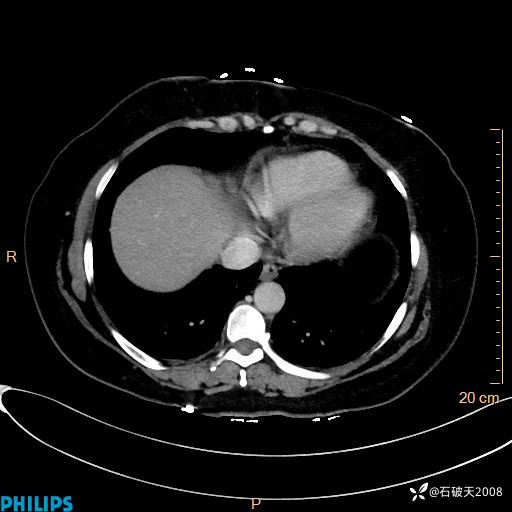

纵隔窗

静脉期